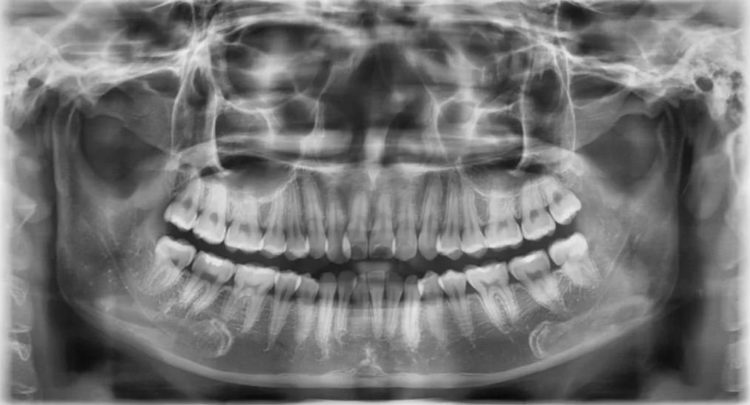

Niềng răng tác động trực tiếp lên xương hàm, do đó người có mật độ xương yếu hoặc đang bị tiêu xương răng nặng cũng thuộc nhóm những người không nên niềng răng. Khi xương không đủ chắc khỏe, việc di chuyển răng sẽ trở nên khó khăn, thậm chí làm tăng nguy cơ lung lay, gãy răng hoặc tụt nướu. Để đảm bảo an toàn, các bác sĩ ở Lạc Việt Intech sẽ chỉ định khách hàng chụp đủ 3 loại phim: phim mặt thẳng, phim sọ nghiêng và phim CT.

Khách hàng cần phải được chụp phim X-quang trước khi niềng răng

Sau đó, bác sĩ cần ứng dụng giải pháp niềng răng X-Matrix với các phần mềm trí tuệ nhân tạo để phân  tích các chỉ số sai lệch răng, tính toán lực kháng xương vỏ và xác định lực chỉnh nha phù hợp. Bác sĩ cũng cần lựa chọn mắc cài cá nhân hóa có độ torque thích hợp để ngăn ngừa chân răng bật ra khỏi xương ổ răng.